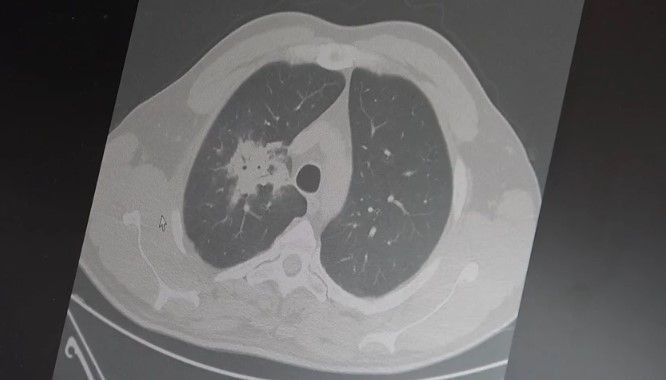

100’den fazla bilimsel çalışmanın incelendiği kapsamlı analizler; elektronik sigaranın özellikle ağız ve akciğer bölgelerinde kanser riskini doğrudan artırdığını gösteriyor.

Bu verilere göre; her iki ürünü de kullananlarda akciğer kanseri riski, sadece sigara içenlere göre tam 4 kat daha fazla.